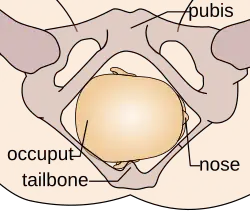

Durante la mecánica del parto, los diámetros menores del feto pasan por los diámetros mayores de la pelvis materna. Con el fin de no quedar encajado en algún punto durante su trayectoria fuera del útero, el neonato pasa por una serie de movimientos naturales que constituyen el mecanismo del parto.

- Descenso: ocurre por acción de la gravedad una vez dilatado el cuello uterino, así como de las poderosas contracciones uterinas y de los músculos abdominales maternos. El descenso tiende a ser lentamente progresivo basado en la estructura pélvica materna.

- Flexión: la cabeza del feto se flexiona, de modo que el mentón fetal hace contacto con su pecho, al encontrarse el primer punto de resistencia del piso pélvico.

- Encajamiento: el diámetro de la cabeza del feto que va desde un hueso parietal al opuesto, llamado diámetro biparietal, alcanza el estrecho superior de la pelvis a nivel de las espinas isquiáticas. Por lo general ocurre en la fase tardía del embarazo, justo al iniciarse el trabajo de parto.

- Rotación interna: ocurre en el estrecho medio de la pelvis, cuando el feto, al continuar su descenso, hace una rotación de 90° en el sentido contrario a las agujas del reloj, de modo de adaptarse a la configuración romboidal de los músculos del piso pélvico, entre el músculo elevador del ano y los ileocoxígeos. Así, la cara del bebé está dirigida mirando hacia el recto materno.

- Extensión: la cabeza del feto atraviesa el canal del parto, se extiende de tal manera que la frente se desplaza primero por el orificio vulvar. La cabeza está por debajo de la sínfisis púbica y ha distendido al máximo el perineo.

- Rotación externa: una vez que ha salido la cabeza, se gira 45° para restaurar su posición original antes de la rotación interna y quedar en posición normal en relación con los hombros. Se denomina por ella la restitución, haciendo el paso de los hombros más factible.

- Expulsión: el hombro púbico tiende a salir primero, seguido por el hombro perineal. El resto del cuerpo sale por sí solo con una leve impulsión materna.

Estos movimientos son todos debido a la relación que existe entre la cabeza ósea y hombros del feto y el anillo óseo de la pelvis materna.

La relación de la fontanela posterior con la pelvis materna determina el diagnóstico de posición. Se distinguen ocho posiciones en la presentación de vértice: I. Occípito ilíaca izquierda anterior (OIIA) en que la fontanela posterior se ubica hacia delante en relación con la pelvis materna y además a la izquierda de la madre. La sutura sagital está orientada oblicuamente. II. Sucesivamente dependiendo de la ubicación de la fontanela posterior (porque la pelvis es siempre la misma) las posiciones serán: